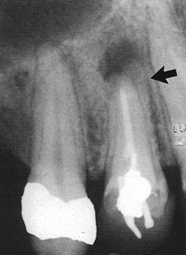

38-letni pacjent zgłasza się do gabinetu stomatologicznego z powodu bólu zęba 14 występującego podczas nagryzania. Badanie kliniczne wykazuje bolesną reakcję na opukiwanie. Co można zauważyć na zamieszczonym poniżej zdjęciu rtg wykonanym w projekcji mezjalno-skośnej u ww. pacjenta?